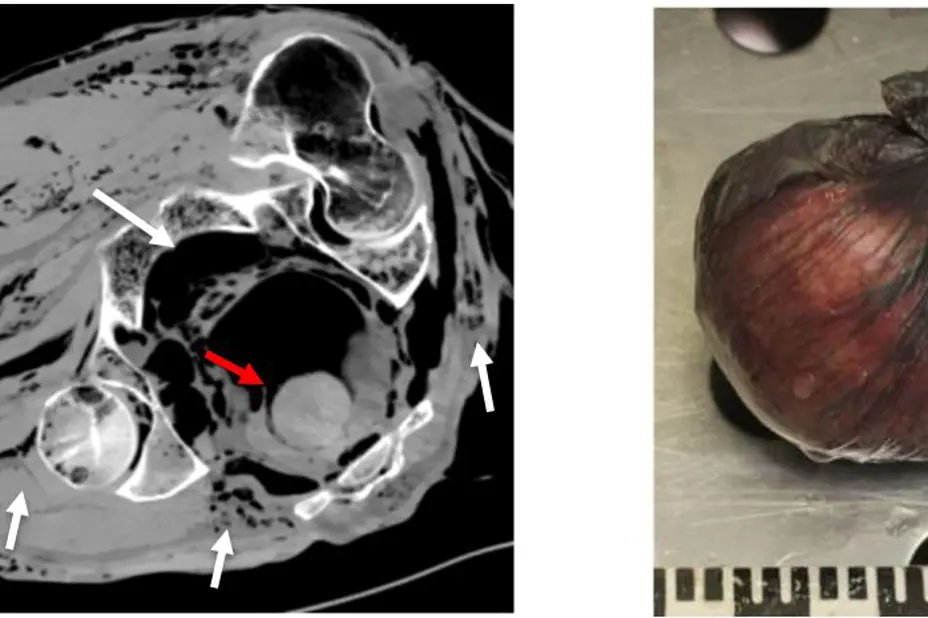

Fig 4. Bildet til venstre er CT-bilde av bekkenet. Avdøde var ikke sett i live på flere måneder. Merk rikelig med gassblærer (hvite piler), men også rund struktur (rød pil) forenlig med et fremmedlegeme i endetarmen. Bildet til høyre viser fremmedlegemet som viste seg å være heroin pakket inn i plast.

Postmortem CT gir ikke bare informasjon om bruddskader eller prosjektiler og fremmedlegemer i kroppen til avdøde personer. CT-bildene kan fremvise blødninger, svulster og ansamlinger av gass, væske og luft. Funnene blir bekreftet ved klassisk obduksjon.

Også forandringene som skjer etter døden har egne karakteristika på CT-bilder. Gassbobler kan oppstå i bløtvev og blodkar allerede få timer etter døden og kan gjøre diagnoser som pneumothorax (luft rundt lungene) og gassembolier (luftbobler i blodkar) krevende å tolke, spesielt om man ikke er vant til å vurdere slike CT-bilder. Fortetninger på et lungebilde må tolkes med stor forsiktighet fordi stuvning av blod i store blodkar kan se ut som blodpropper og stuvning i kapillærer kan være «indre dødsflekker». Det vil si uttrykk for at tyngdekraften har ført til at blodet synker ned i lavest liggende områder.